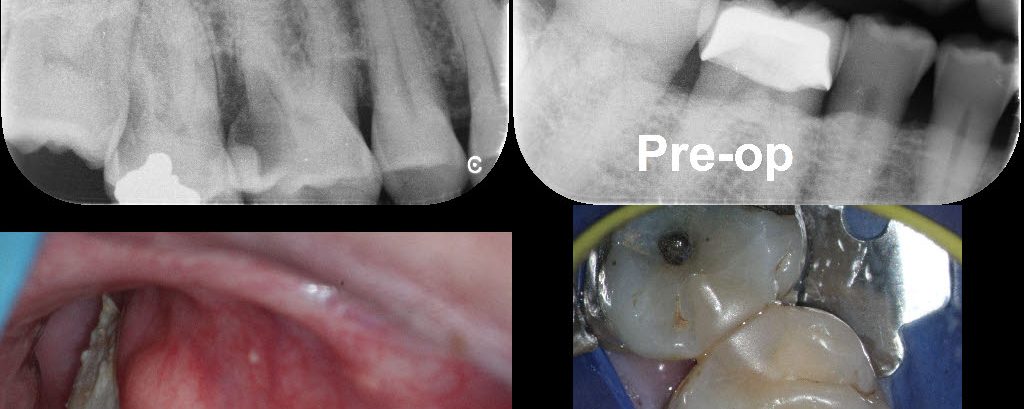

June 25, 2018 13 comments

Selective Caries Removal (SCR) is a paradigm shift from traditional views on the treatment of caries (i.e. all caries needs to be removed). In most situations I subscribe to the traditional view but there are situations where removing all the caries will necessitate complete RCT which may not be feasible (e.g. the very young and […]